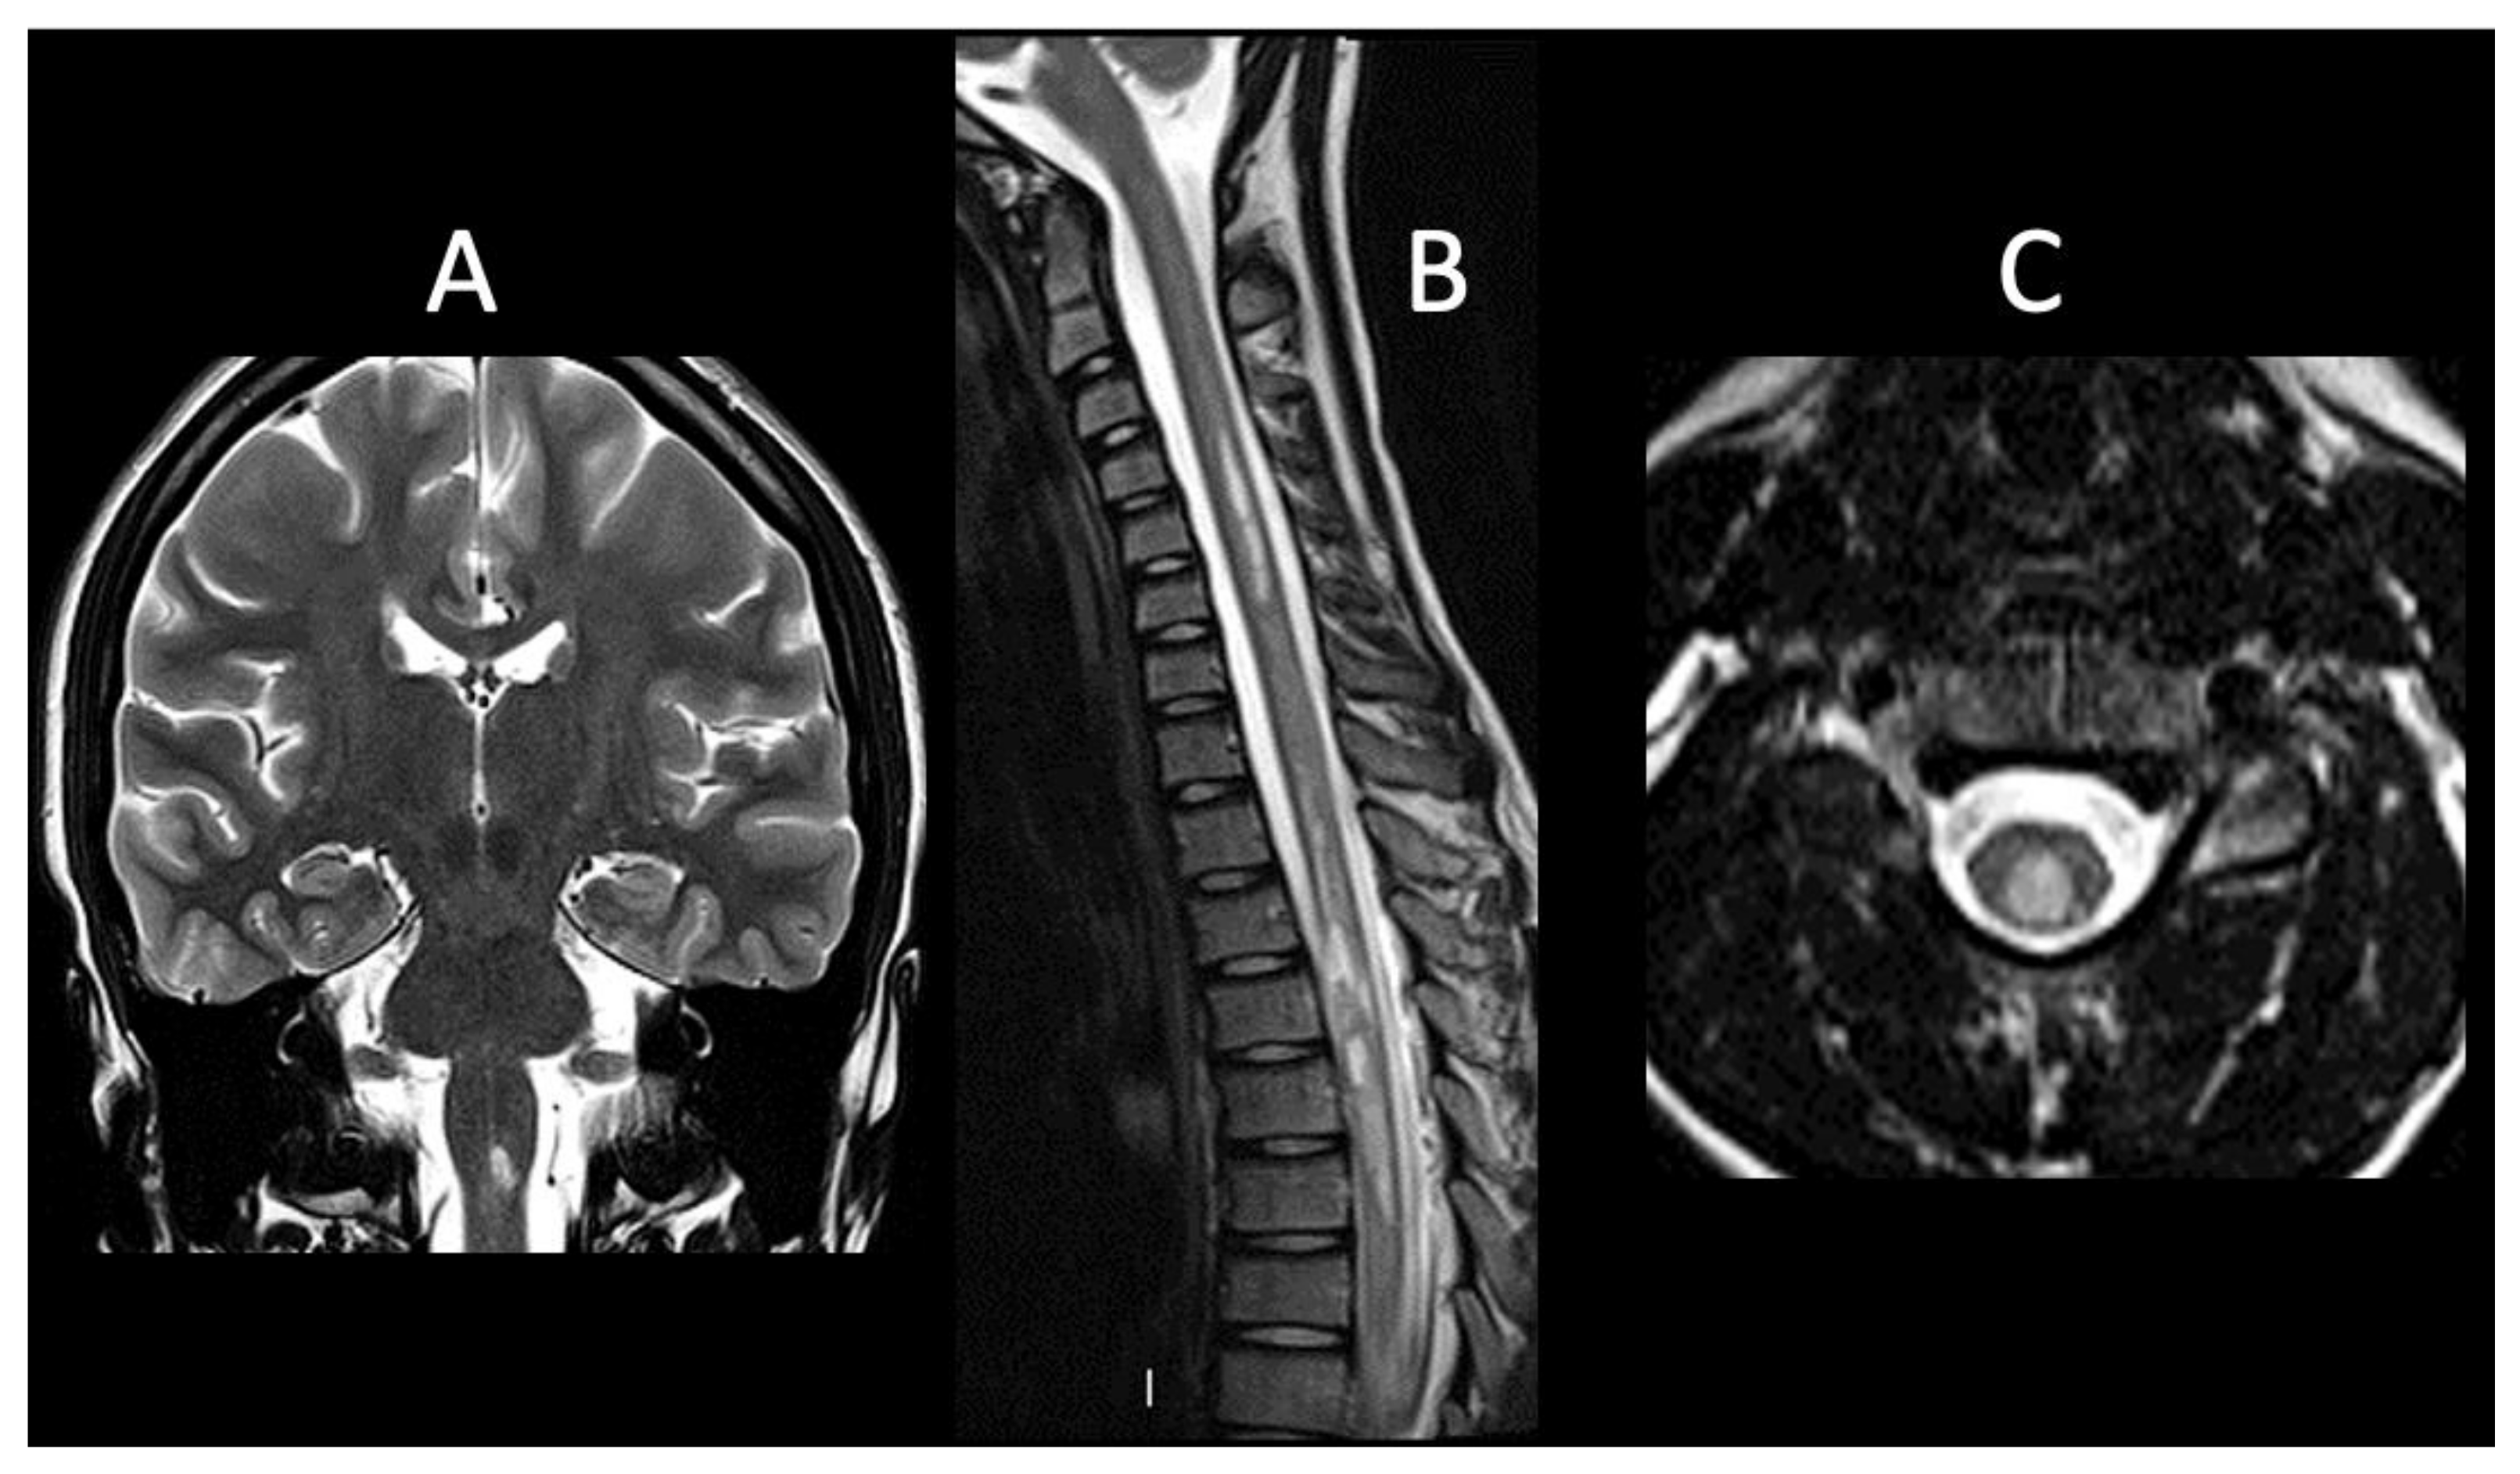

| 1 | F, 16 | Headache, vomiting, vertigo | Right centrum semiovale, near the trigone and the temporal horn of the right ventricle, pons, medulla oblongata, dorsal spine | Yes | AQP4-IgG positive | No | Normal VEPs, SEPs and MEPs | 3 | IVMP | Monophasic | Oral CS, HCQ, MMF | 0 |

| 2 | F, 9 | Bilateral ON, progressive bilateral lower limb hyposthenia | Right frontal subcortical region, corpus callosum, cervical and dorsal spine | Yes | AQP4-IgG positive | Yes | Abnormal VEPs and SEPs (MEPs not available) | 4 | IVMP | Relapsing | Oral CS, RTX, AZA | 5 |

| 3 | F, 8 | Bilateral ON | Bilateral optic nerves | Yes, left optic nerve | AQP4-IgG positive | No | Abnormal VEPs, normal SEPs and MEPs | 4 | IVMP, PE | Monophasic | RTX | 0 |

| 4 | M, 15 | Progressive right lower limb paresis | From cervical spine to the conus medullaris | No | AQP4-IgG and MOG-IgG negative | No | Abnormal VEPs, SEPs and MEPs | 8.5 | IVMP | Relapsing | RTX, MMF | 0 |

| 5 | M, 10 | Right lower limb paresis, sensory level at T10-T11 | Diffuse bilateral cerebral involvement, cervical spine | Yes | AQP4-IgG and MOG-IgG negative | No | Abnormal VEPs, SEPs and MEPs | 9 | IVMP, PE | Relapsing | RTX | 7.5 |

| 6 | M, 13 | Gait ataxia, bilateral lower limb paresthesia, pyramidal signs, sensory level at T10 | Dorsal spine | Yes | AQP4-IgG and MOG-IgG negative | No | Abnormal VEPs (SEPs and MEPs not available) | 6 | IVMP | Monophasic | Oral CS | 0 |

| 7 | M, 11 | Unilateral ON | Left optic nerve and cervical spine | Yes | AQP4-IgG and MOG-IgG negative | No | Abnormal VEPs, normal SEPs and MEPs | 2 | IVMP | Relapsing | IVIG | 1 |